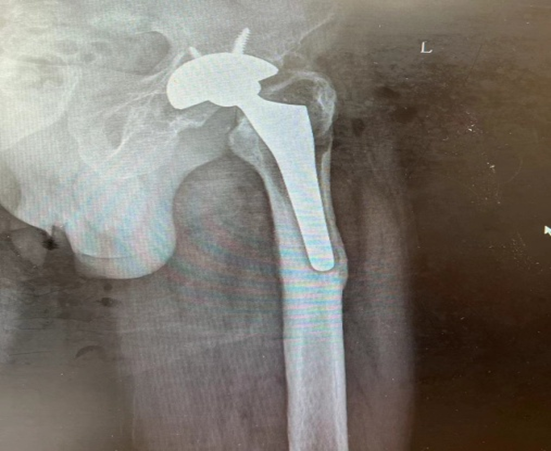

经过缜密的术前规划,在排除手术禁忌症后,科室负责人贺宝东主任医师带领科室团队为陈大伯成功完成左侧人工髋关节翻修术。术中取出股骨柄假体及磨损的聚乙烯假体,清理周围不健康组织,判断合金臼杯假体稳定性与术前评估一致,更换新的聚乙烯内衬、骨水泥型长柄及合金股骨头假体。

( 取出松动、磨损的假体 )